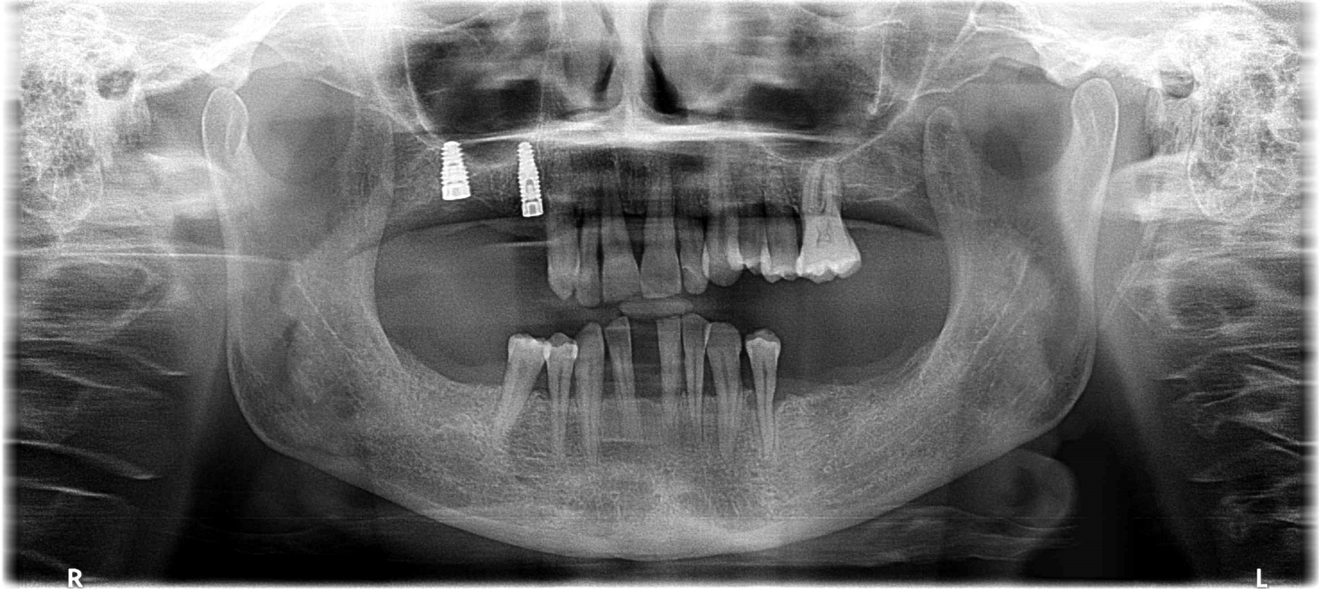

The 58-year-old, non-smoking and systemically healthy female patient was referred by her dentist to our dental clinic for implant treatment. The patient’s main complaints were poor aesthetics in the upper jaw, including a high smile line and distinct tooth pattern anomalies in the anterior maxilla (Figs. 1 & 2), as well as masticatory discomfort. Teeth #17, 15 and 27 were missing and had not undergone any prosthetic treatment, whereas the five missing teeth in the premolar and molar areas on both sides of the mandible had been replaced with a removable partial denture. All remaining teeth were affected by Stage IV periodontitis according to the 2017 Classification of Periodontal and Peri‐implant Diseases and Conditions, displaying a mean periodontal pocket depth of 5.6 mm.7 Mean bleeding on probing and mean plaque index were 70% and 80%, respectively. With respect to periodontal parameters, as well as to oral hygiene measures (visible calculus and dental plaque), the patient’s oral hygiene was graded as poor. The patient had been treated elsewhere with two implants in the posterior maxilla in order to replace the right first premolar and first molar (Fig. 3). She had a thick flat biotype, according to a definition introduced in 1977.8, 9

Fig. 4: CBCT scan showing the bone condition of the maxillary teeth. Vertical resorption and reduced thickness of the buccal bone plate of the right and left central incisors were evident.